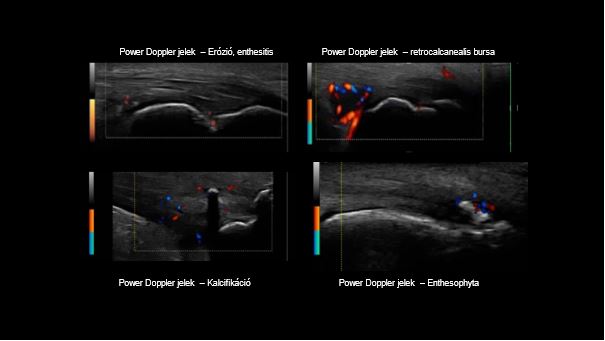

Enthesitis okozta UH elváltozások

B-mód UH vezérelt folyadékaspiráció, Power Doppler módú felvétel.